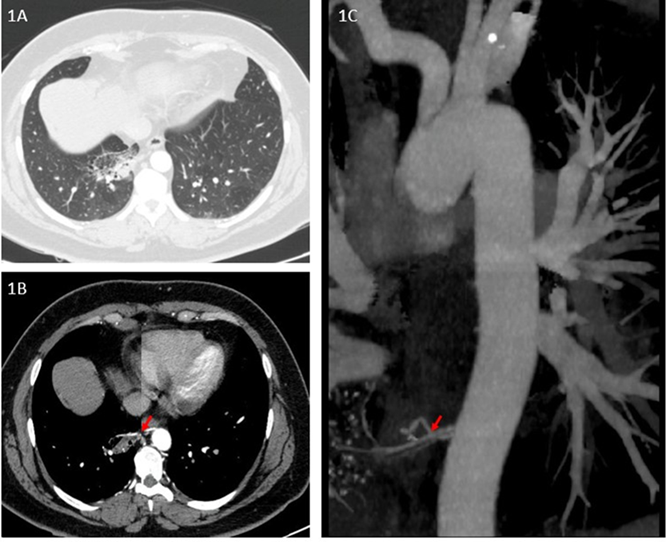

Estudios complementarios. Tomografías adicionales realizadas en hospitales de referencia nacional (enero–mayo 2024) confirmaron un área focal seudonodular en el lóbulo inferior derecho, asociada a un vaso sistémico aberrante proveniente de la aorta torácica (ver figuras 1A,1B,1C).

Figuras 1. Estudios complementarios

Figura 1ª. Angiotomografía de tórax muestra parénquima pulmonar del lóbulo inferior derecho con bronquiectasias quísticas. 1B. Ventana mediastinal muestra flecha roja señala arteria anómala que nutre secuestro pulmonar. 1C. En reconstrucción de aorta torácica y sus ramas, flecha roja marca el origen de la arteria anómala en la aorta torácica que confirma secuestro pulmonar.